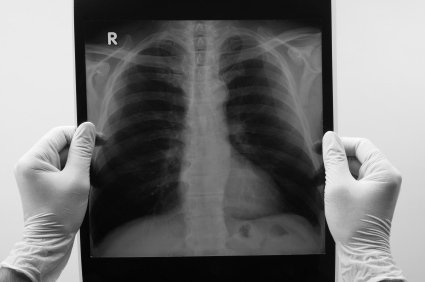

O diagnóstico de suspeita do pneumotórax pode ser feito através do histórico clínico e do exame físico, todavia, a confirmação depende de uma radiografia de tórax, a qual mostrará certa quantidade de ar entre os pulmões e a parede torácica. Dados mais precisos podem ainda ser obtidos por meio de uma tomografia computadorizada, útil sobretudo nos casos de pneumotórax espontâneo e de pequeno volume.